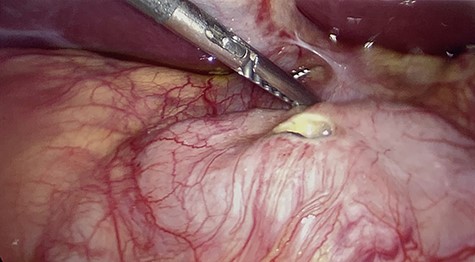

All of the standard preoperative measures were taken and the patient was prepped and draped for laparoscopic cholecystectomy. Ports were placed in a typical fashion for this operation, with A 12 mm Hasson trocar placed in a supraumbilical position, and 5 mm trocars placed in the epigastrium and RUQ x2. Upon insertion of the laparoscope, the uterus was still large in the pelvis and there was a small amount of bloody fluid in the abdomen. The fundus of the gallbladder was grasped and retracted cephalad. With this maneuver it appeared that the duodenum had fused itself to the infundibulum of the gallbladder. Upon gently peeling the duodenum off of the gallbladder, it became obvious that there was a perforated duodenal in the first portion of the anterior duodenum and had been the gallbladder that sealed the perforation (Figs 4–6). The gallbladder showed signs of erosion at the site where it patched the duodenum as well (Fig. 6). At this time we proceeded with laparoscopic cholecystectomy first, prior to addressing the duodenum. Once successfully completed with the cholecystectomy, we performed a laparoscopic graham patch with our existing ports, which can be seen in Fig. 7. A #10 flat JP was inserted in the region of the graham patch. The abdomen was irrigated and then suctioned clean. The repair was confirmed by placing underwater with the second portion of the duodenum compressed, while anesthesia insufflated the stomach/duodenum through an OG tube. The patient tolerated the operation well, extubated, and transported to recovery.

First portion of duodenum with perforated ulcer. Gallbladder retracted out of frame.